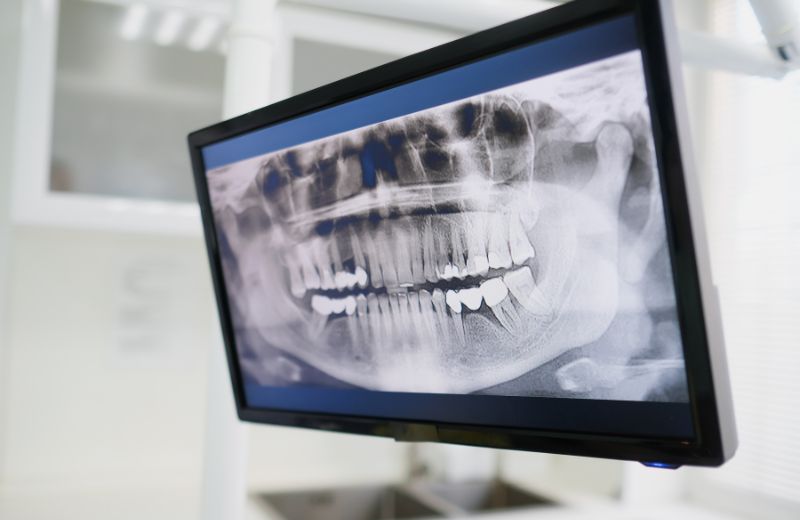

Our clinic is equipped with OPG and Lateral Cephalometric X-ray facilities, offering detailed digital imaging for accurate diagnosis and treatment planning. These advanced radiographs allow our dentists and orthodontists to view the full structure of your teeth, jaw, and facial profile with precision. This technology is essential for orthodontics, implants, and surgical procedures, ensuring every treatment is tailored to your unique dental anatomy. We prioritize safe, low-radiation imaging while delivering clarity and confidence in every diagnosis.

It’s a full-mouth panoramic X-ray that shows teeth, jaw, and bone structure.

It helps orthodontists and surgeons plan treatments like braces or surgery.